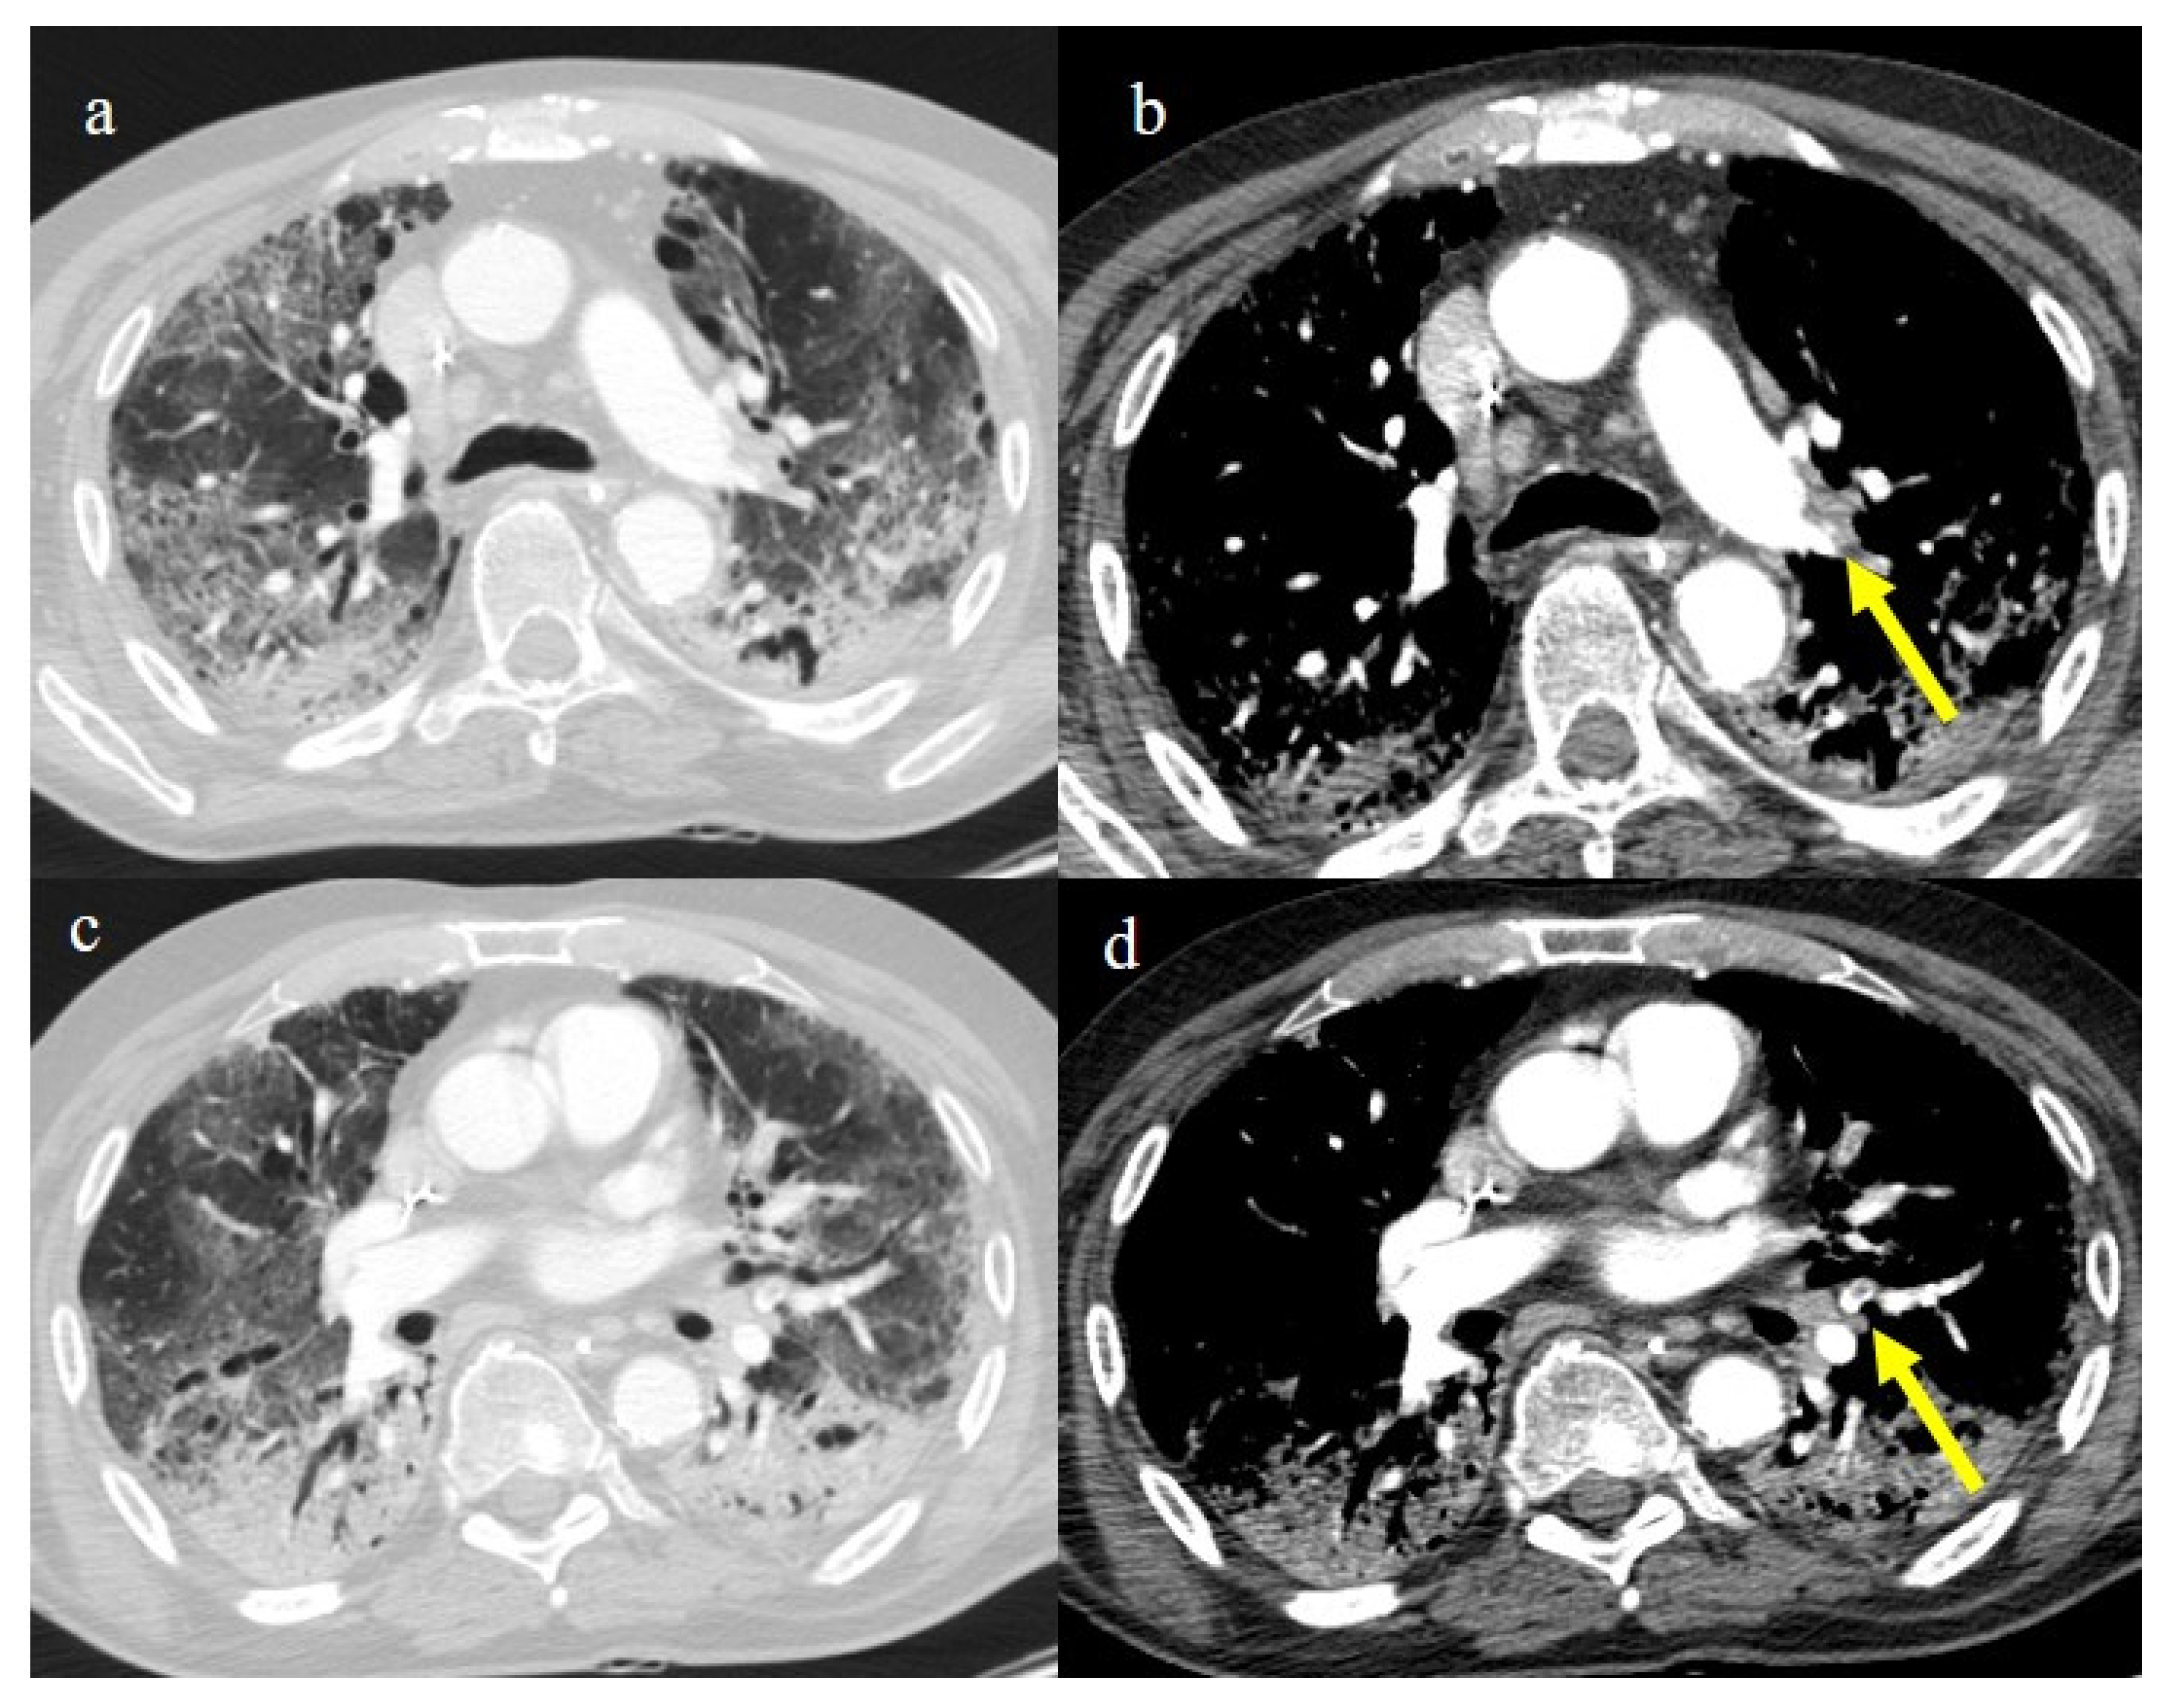

- Bonaffini, P.A.; Franco, P.N.; Bonanomi, A.; Giaccherini, C.; Valle, C.; Marra, P.; Norsa, L.; Marchetti, M.; Falanga, A.; Sironi, S. Ischemic and hemorrhagic abdominal complications in COVID-19 patients: Experience from the first Italian wave. Eur. J. Med. Res. 2022, 27, 1–9. [Google Scholar] [CrossRef]

- Peshevska-Sekulovska, M.; Boeva, I.; Sekulovski, M.; Zashev, M.; Peruhova, M. Gastrointestinal Ischemia—Stumbling Stone in COVID-19 Patients. Gastroenterol. Insights 2022, 13, 206–217. [Google Scholar] [CrossRef]

- Norsa, L.; Bonaffini, P.A.; Caldato, M.; Bonifacio, C.; Sonzogni, A.; Indriolo, A.; Valle, C.; Furfaro, F.; Bonanomi, A.; Franco, P.N.; et al. Intestinal ischemic manifestations of SARS-CoV-2: Results from the ABDOCOVID multicentre study. World J. Gastroenterol. 2021, 27, 5448–5459. [Google Scholar] [CrossRef]

- Bhayana, R.; Som, A.; Li, M.D.; Carey, D.E.; Anderson, M.A.; Blake, M.A.; Catalano, O.; Gee, M.S.; Hahn, P.F.; Harisinghani, M.; et al. Abdominal Imaging Findings in COVID-19: Preliminary Observations. Radiology 2020, 297, E207–E215. [Google Scholar] [CrossRef]

- Caruso, D.; Zerunian, M.; Pucciarelli, F.; Lucertini, E.; Bracci, B.; Polidori, T.; Guido, G.; Polici, M.; Rucci, C.; Iannicelli, E.; et al. Imaging of abdominal of abdominal complications of COVID-19 infection. BJR Open 2021, 2, 20200052. [Google Scholar] [CrossRef]

- Ojha, V.; Mani, A.; Mukherjee, A.; Kumar, S.; Jagia, P. Mesenteric ischemia in patients with COVID-19: An updated systematic review of abdominal CT findings in 75 patients. Abdom. Imaging 2021, 47, 1565–1602. [Google Scholar] [CrossRef]

- Boraschi, P.; Giugliano, L.; Mercogliano, G.; Donati, F.; Romano, S.; Neri, E. Abdominal and gastrointestinal manifestations in COVID-19 patients: Is imaging useful? World J. Gastroenterol. 2021, 27, 4143–4159. [Google Scholar] [CrossRef]

- Keshavarz, P.; Rafiee, F.; Kavandi, H.; Goudarzi, S.; Heidari, F.; Gholamrezanezhad, A. Ischemic gastrointestinal complications of COVID-19: A systematic review on imaging presentation. Clin. Imaging 2020, 73, 86–95. [Google Scholar] [CrossRef] [PubMed]

- Gupta, A.; Sharma, O.; Srikanth, K.; Mishra, R.; Tandon, A.; Rajput, D. Review of Mesenteric Ischemia in COVID-19 Patients. Indian J. Surg. 2022, 85, 313–321. [Google Scholar] [CrossRef]

- Reginelli, A.; Genovese, E.; Cappabianca, S.; Iacobellis, F.; Berritto, D.; Fonio, P.; Coppolino, F.; Grassi, R. Intestinal Ischemia: US-CT findings correlations. Crit. Ultrasound J. 2013, 5, S7. [Google Scholar] [CrossRef]